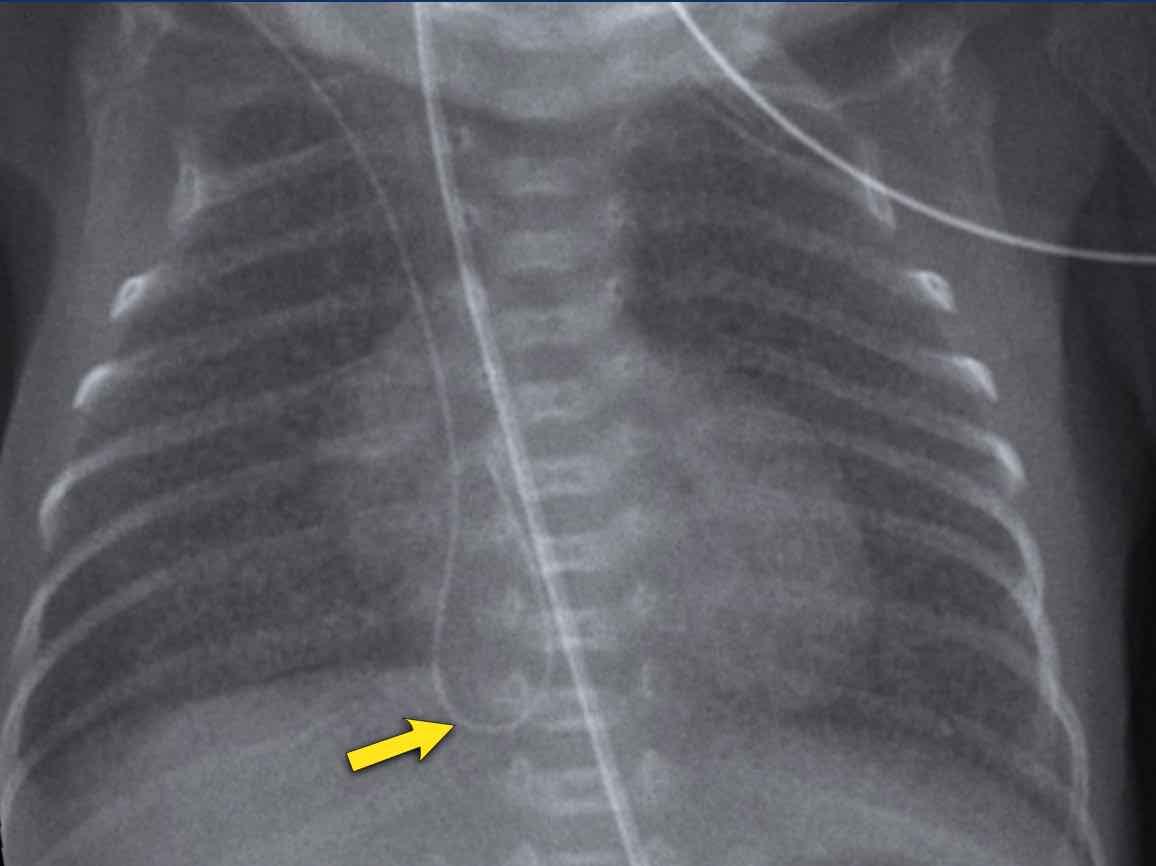

29 tuần + 1, ngày đầu tiên. CPAP.

Findings:

- Reticulogranular opacification

of lungs - Air bronchogram

- Consolidation in the right lower lobe

- Heart, vessels and

diaphragm are poorly defined. - Đặt sai vị trí catheter tĩnh mạch rốn (mũi tên), có thể nằm trong tĩnh mạch phổi.

- Nasogastric tube (NG tube) in good position.

Đây là trường hợp nặng của hội chứng suy hô hấp (RDS).

Chẩn đoán phân biệt bao gồm nhiễm trùng phổi do tình trạng đông đặc không đối xứng.